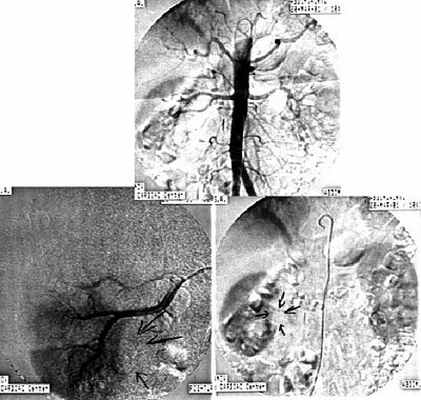

6. Ангиография:

• Обычная ангиография

о Гиповаскулярное образование (редко-аваскулярное или гиперваскулярное)

Аортоартериография почек. Брюшная аорта и ее ветви без особенностей. Размеры, положение, форма почек обычные. Нефрограмма интенсивная, гомогенная. В нижнем полюсе правой почки определяется аваскулярное образование шаровидной формы, не накапливающее контрастное вещество, до 30 мм в диаметре.

Заключение: По ангиографической картине больше данных о кистозном доброкачественном образовании нижнего полюса правой почки (рис. 6).

В нижнем полюсе правой почки определяется аваскулярное образование шаровидной формы, не накапливающее контрастное вещество, до 30 мм в диаметре (стрелки).